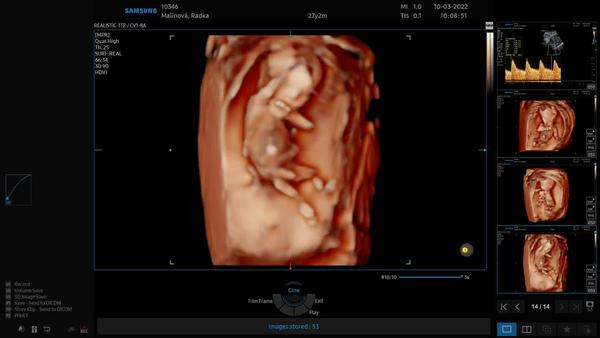

z těchto fotek určit bohužel nelze. ☹